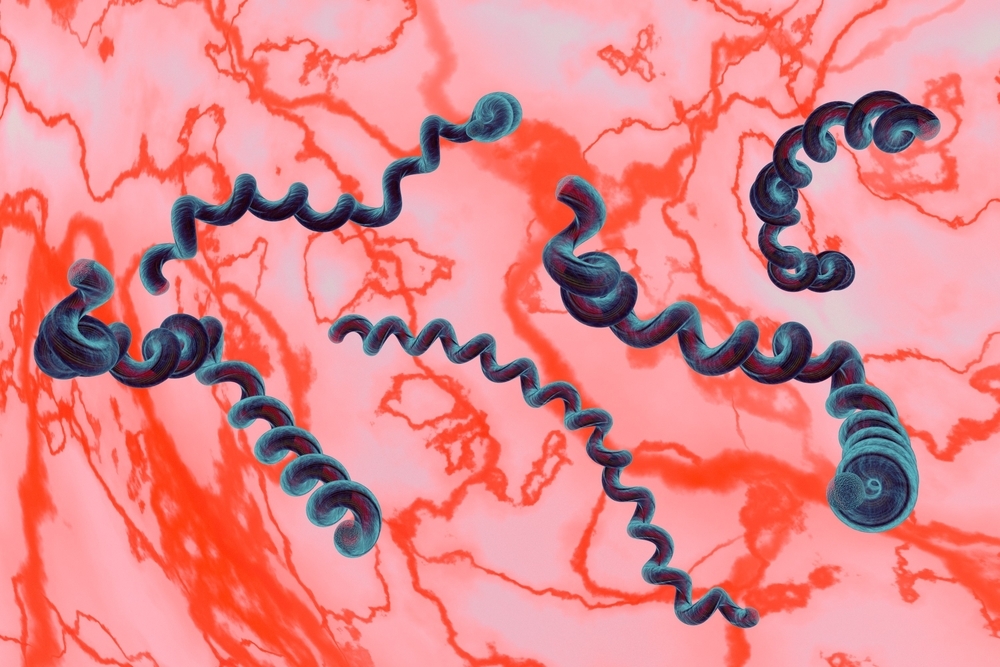

Лептоспиры: фотографии удивительных микроорганизмов